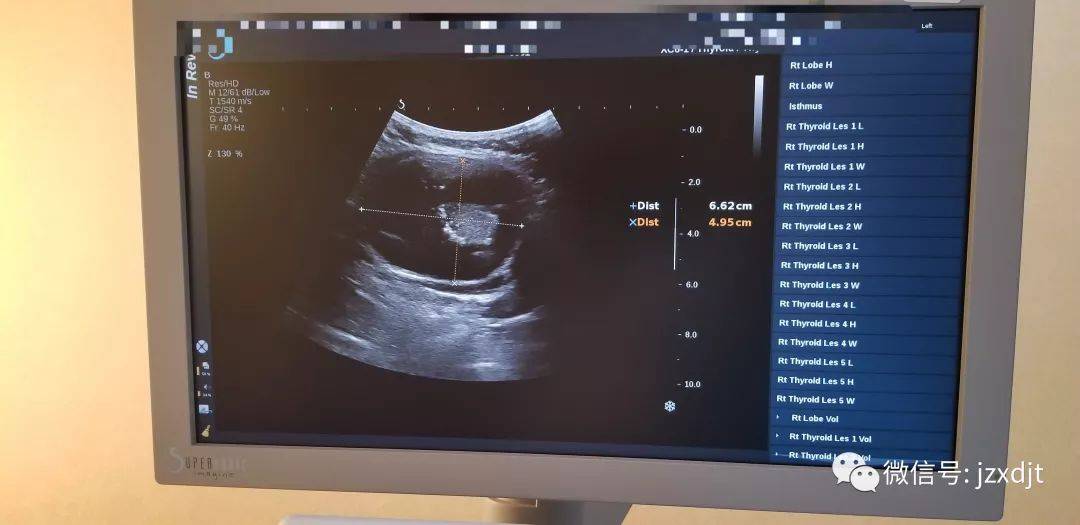

甲状腺b超图图解

史上最实用甲状腺超声诊断有图有真相